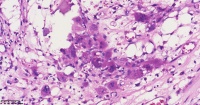

请教老师们这些巨细胞有什么临床意义?

性别

女

年龄

61岁

临床诊断

股骨头骨折

一般病史

标本名称

股骨头组织

大体所见

股骨头骨折处组织

多核吞噬细胞,有纤维素性坏死

是一种反应性改变。